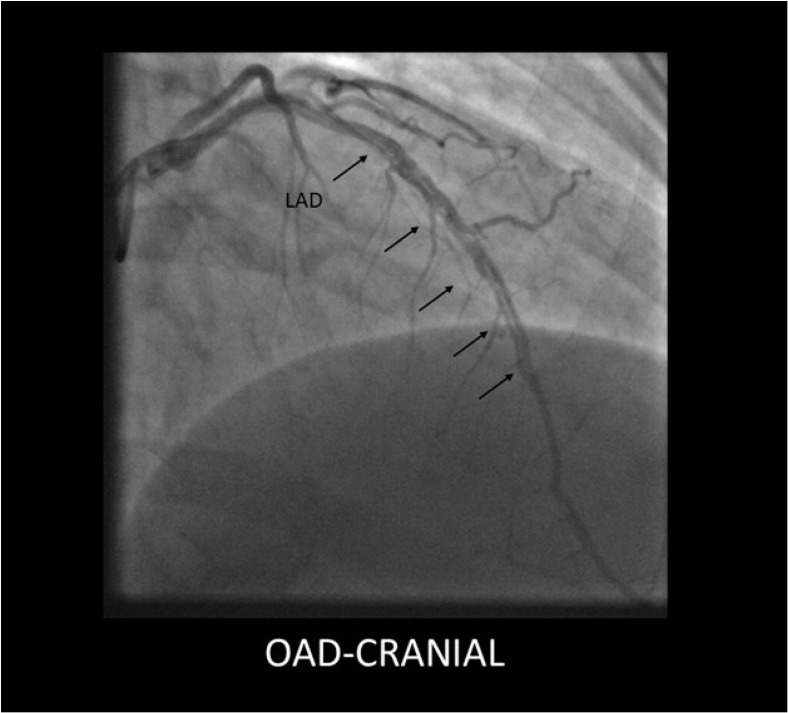

自发性冠状动脉剥离(SCAD)是急性冠状动脉综合征(ACS)的一种日益被认识的非动脉粥样硬化性原因,特别是在年轻女性中。这篇综述概述了SCAD独特的病理生理学,它与潜在的动脉病变如纤维肌肉发育不良有关,并强调了先进的血管内成像对准确诊断的关键作用。详细介绍了治疗的根本转变,有证据表明,由于血管自发愈合率高,稳定患者倾向于采用保守策略,为高风险病例保留技术上具有挑战性的侵入性干预措施。重要的是,本综述还涉及了长期结果,注意到复发率和主要不良心脏事件(MACE),持续胸痛的高患病率,以及β受体阻滞剂治疗在二级预防中的核心作用。最终,SCAD需要从标准的ACS协议转向个性化的方法,强调准确的诊断、谨慎的初始管理和警惕的长期随访。

Spontaneous coronary artery dissection (SCAD) is an increasingly recognized, non-atherosclerotic cause of acute coronary syndrome (ACS), particularly in younger women. This comprehensive review outlines SCAD's unique pathophysiology, which is linked to underlying arteriopathies like fibromuscular dysplasia, and highlights the critical role of advanced intravascular imaging for accurate diagnosis. A fundamental shift in management is detailed, with evidence favoring a conservative strategy for stable patients due to high rates of spontaneous vessel healing, reserving technically challenging invasive interventions for high-risk cases. Importantly, this review also addresses long-term outcomes, noting significant rates of recurrence and Major Adverse Cardiac Events (MACE), a high prevalence of persistent chest pain, and the central role of beta-blocker therapy in secondary prevention. Ultimately, SCAD requires a departure from standard ACS protocols towards a personalized approach that emphasizes accurate diagnosis, cautious initial management, and vigilant long-term follow-up.